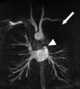

Occlusion of pulmonary vein